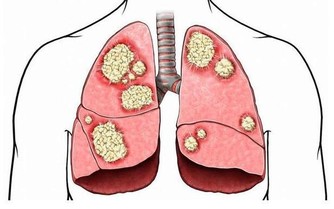

由於現代生活節奏比較快,人們在飲食上總是出現不規律的狀態,經常飢一頓飽一頓,暴飲暴食,其實這對胃是極其不利的,很容易造成胃部損傷,影響人體健康。胃作為消化的主要器官,如果出現健康問題,將會引起胃酸分泌過多、胃潰瘍等症狀。

胃酸是從胃液中分泌出來的一種鹽酸,能夠幫助人體消化食物,但胃酸要控制在一定的範圍之內,如果胃酸過少,會影響人體的消化,易引發營養不良等症狀;

胃酸分泌過多,會刺激到胃粘膜,導致胃出血以及口臭。對於胃酸引起的口臭,除了要養腸胃,還要做好這4件事,預防胃病口臭。